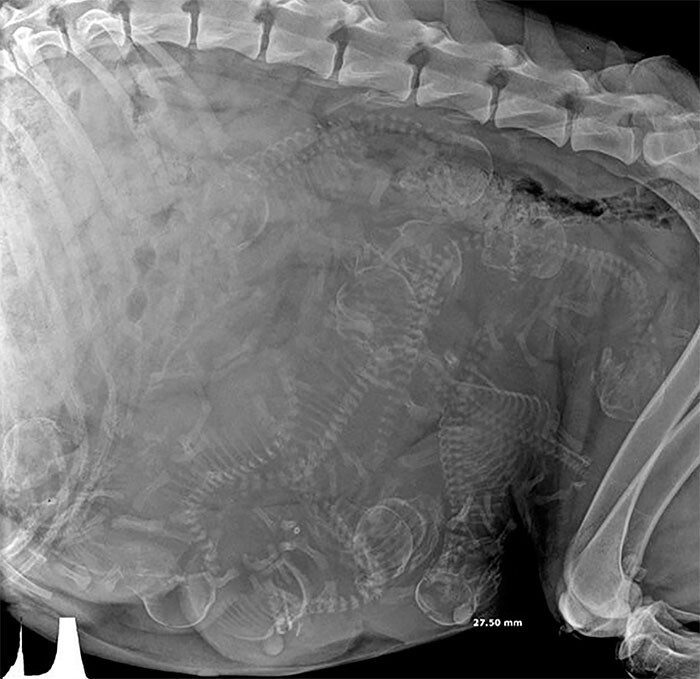

Рентгеновский снимок беременной собаки